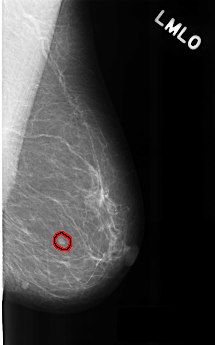

C_0303_1.LEFT_MLO

LEFT_MLO LINES 4480 PIXELS_PER_LINE 2784 BITS_PER_PIXEL 12 RESOLUTION 50 OVERLAY

FILE: C_0303_1.LEFT_MLO.OVERLAY

TOTAL_ABNORMALITIES 1

ABNORMALITY 1

LESION_TYPE MASS SHAPE LOBULATED MARGINS CIRCUMSCRIBED

ASSESSMENT 3

SUBTLETY 5

PATHOLOGY BENIGN

TOTAL_OUTLINES 1

BOUNDARY